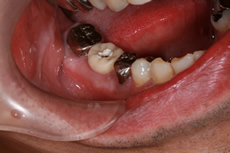

インプラント症例

術前